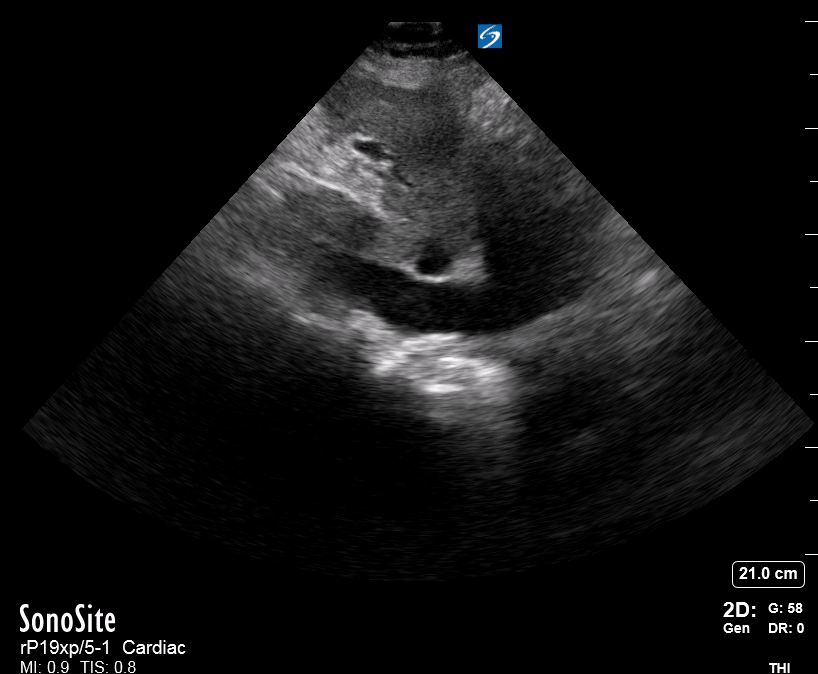

The IVC diameter changes depending on intravascular volume status, and normally, the IVC collapses during spontaneous inspiration. Therefore, the IVC diameter represents a non-invasive method for estimating central venous pressure (CVP). The evidence suggests that in spontaneously breathing patients, there is a good correlation between the sonographic estimation of CVP and values measured with invasive methods (2). IVC filling and CVP, however, allow only a rough correlation with volume status, and the sonographic estimation of preload should at least include the assessment of the LV and the Lung. Thus, it is better to think of IVC filling as an indicator of fluid tolerance, instead of a determinant of fluid responsiveness (6).

IVC exploration is best from the subxiphoid approach with longitudinal and transverse images. The IVC should be assessed in terms of overall size and collapsibility. The diameter is typically measured at its largest (end of expiration) at 1-2 cm distal to where the hepatic veins join the vena cava. An IVC diameter of ≥ 2 cm, especially with minimal or no collapsibility, is considered plethoric and correlates with increased RA pressure. An IVC of < 1 cm, particularly with complete collapse, is considered flat and indicates low preload and potential fluid responsiveness. An IVC diameter between 1 and 2 cm is typically normal.

PITFALLS

In a long-axis view, beware of not sliding off the centre of the vessel, as this will underestimate the size of the IVC and overestimate its collapse. Obtaining long and short axis views may help avoid this pitfall. Another mistake is confusing the descending aorta for the IVC, particularly when scanning in long-axis. Although the IVC may appear to pulsate, the aorta has a thicker wall, and its position is to the patient’s left. Following the IVC upwards will reveal the hepatic veins junction and the entrance to the RA, while the aorta will travel behind the heart. The IVC moves both anterolaterally and craniocaudally with inspiration, and this should be considered during visualization or measuring. For this very reason, measuring in M-mode is not recommended as it would not be accurate.